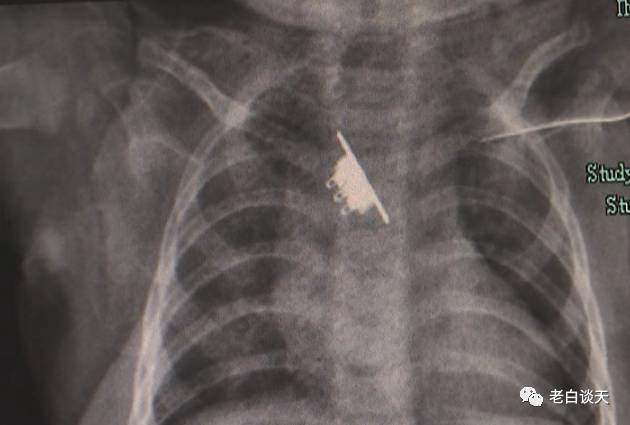

Phim chụp X-Quang cho thấy có một dị vật nằm trong cổ họng của bé gái. Nhưng các bác sĩ cho biết thêm đó chỉ là một phần, một phần khác không xuất hiện trong bức ảnh mà đang mắc kẹt ở thực quản. Thực quản của trẻ rất mỏng có thể gây ra nhiều tổn thương, thậm chí là rách thực quản, nguy hiểm hơn rất nhiều so với người lớn.